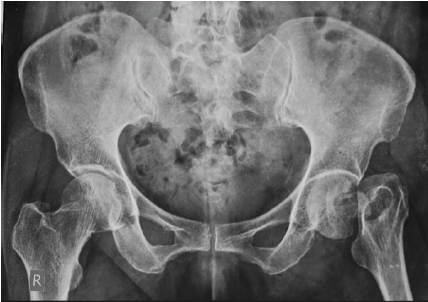

Aneurysmal Bone Cyst Presenting as a Pathological Subtrochanteric Femur Fracture in an Adolescent: A Case Report

Chandrashekhar R Rai , Sandeep V Gavhale , Vijaysing Chandele , Alok P Yadav , Chinmay S Torne , Vishal B Karpe

………………………………p.89-93